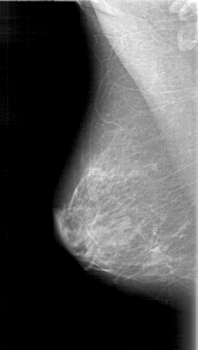

D_4024_1.LEFT_MLO

LEFT_MLO LINES 5386 PIXELS_PER_LINE 3076 BITS_PER_PIXEL 12 RESOLUTION 43.5 OVERLAY